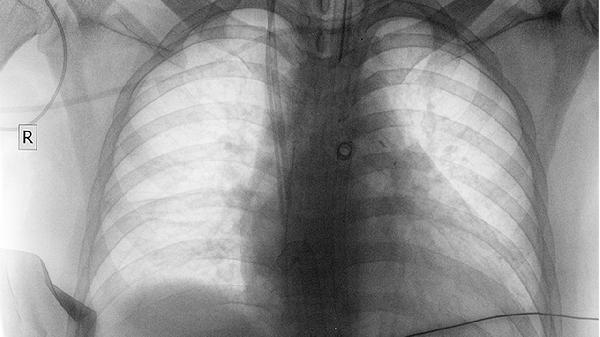

當(dāng)癌胚抗原超過(guò)20微克/升或伴隨體重下降、便血、腹痛等癥狀時(shí),腫瘤概率顯著增加。結(jié)直腸癌患者約70%會(huì)出現(xiàn)該指標(biāo)升高,胃癌和胰腺癌陽(yáng)性率約為50%。乳腺癌、肺癌等非消化道腫瘤也可能導(dǎo)致輕度異常。需通過(guò)胃腸鏡、腹部CT、腫瘤PET-CT等檢查明確病灶位置。對(duì)于有家族腫瘤史或年齡超過(guò)40歲的高危人群,即使無(wú)癥狀也應(yīng)完善篩查。